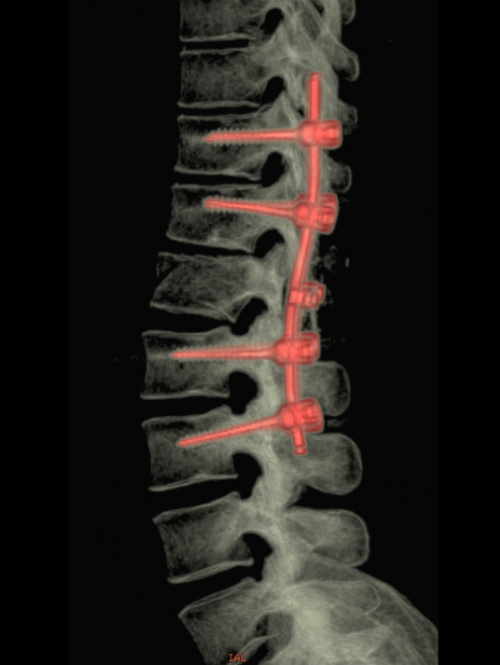

La voie postérieure : à ciel ouvert (Figure 1), qui permet la réduction, la libération de structures nerveuses, et l’ostéosynthèse (avec ou sans greffe) par la mise en place de vis pédiculaires ou de crochets ; de manière minimale-invasive telles que les fixations percutanées par voie postérieure, l’injection de ciment et l’expansion vertébrale avec des ballonnets, stents ou crics.

Figure 1 : Ostéosynthèse classique à ciel ouvert